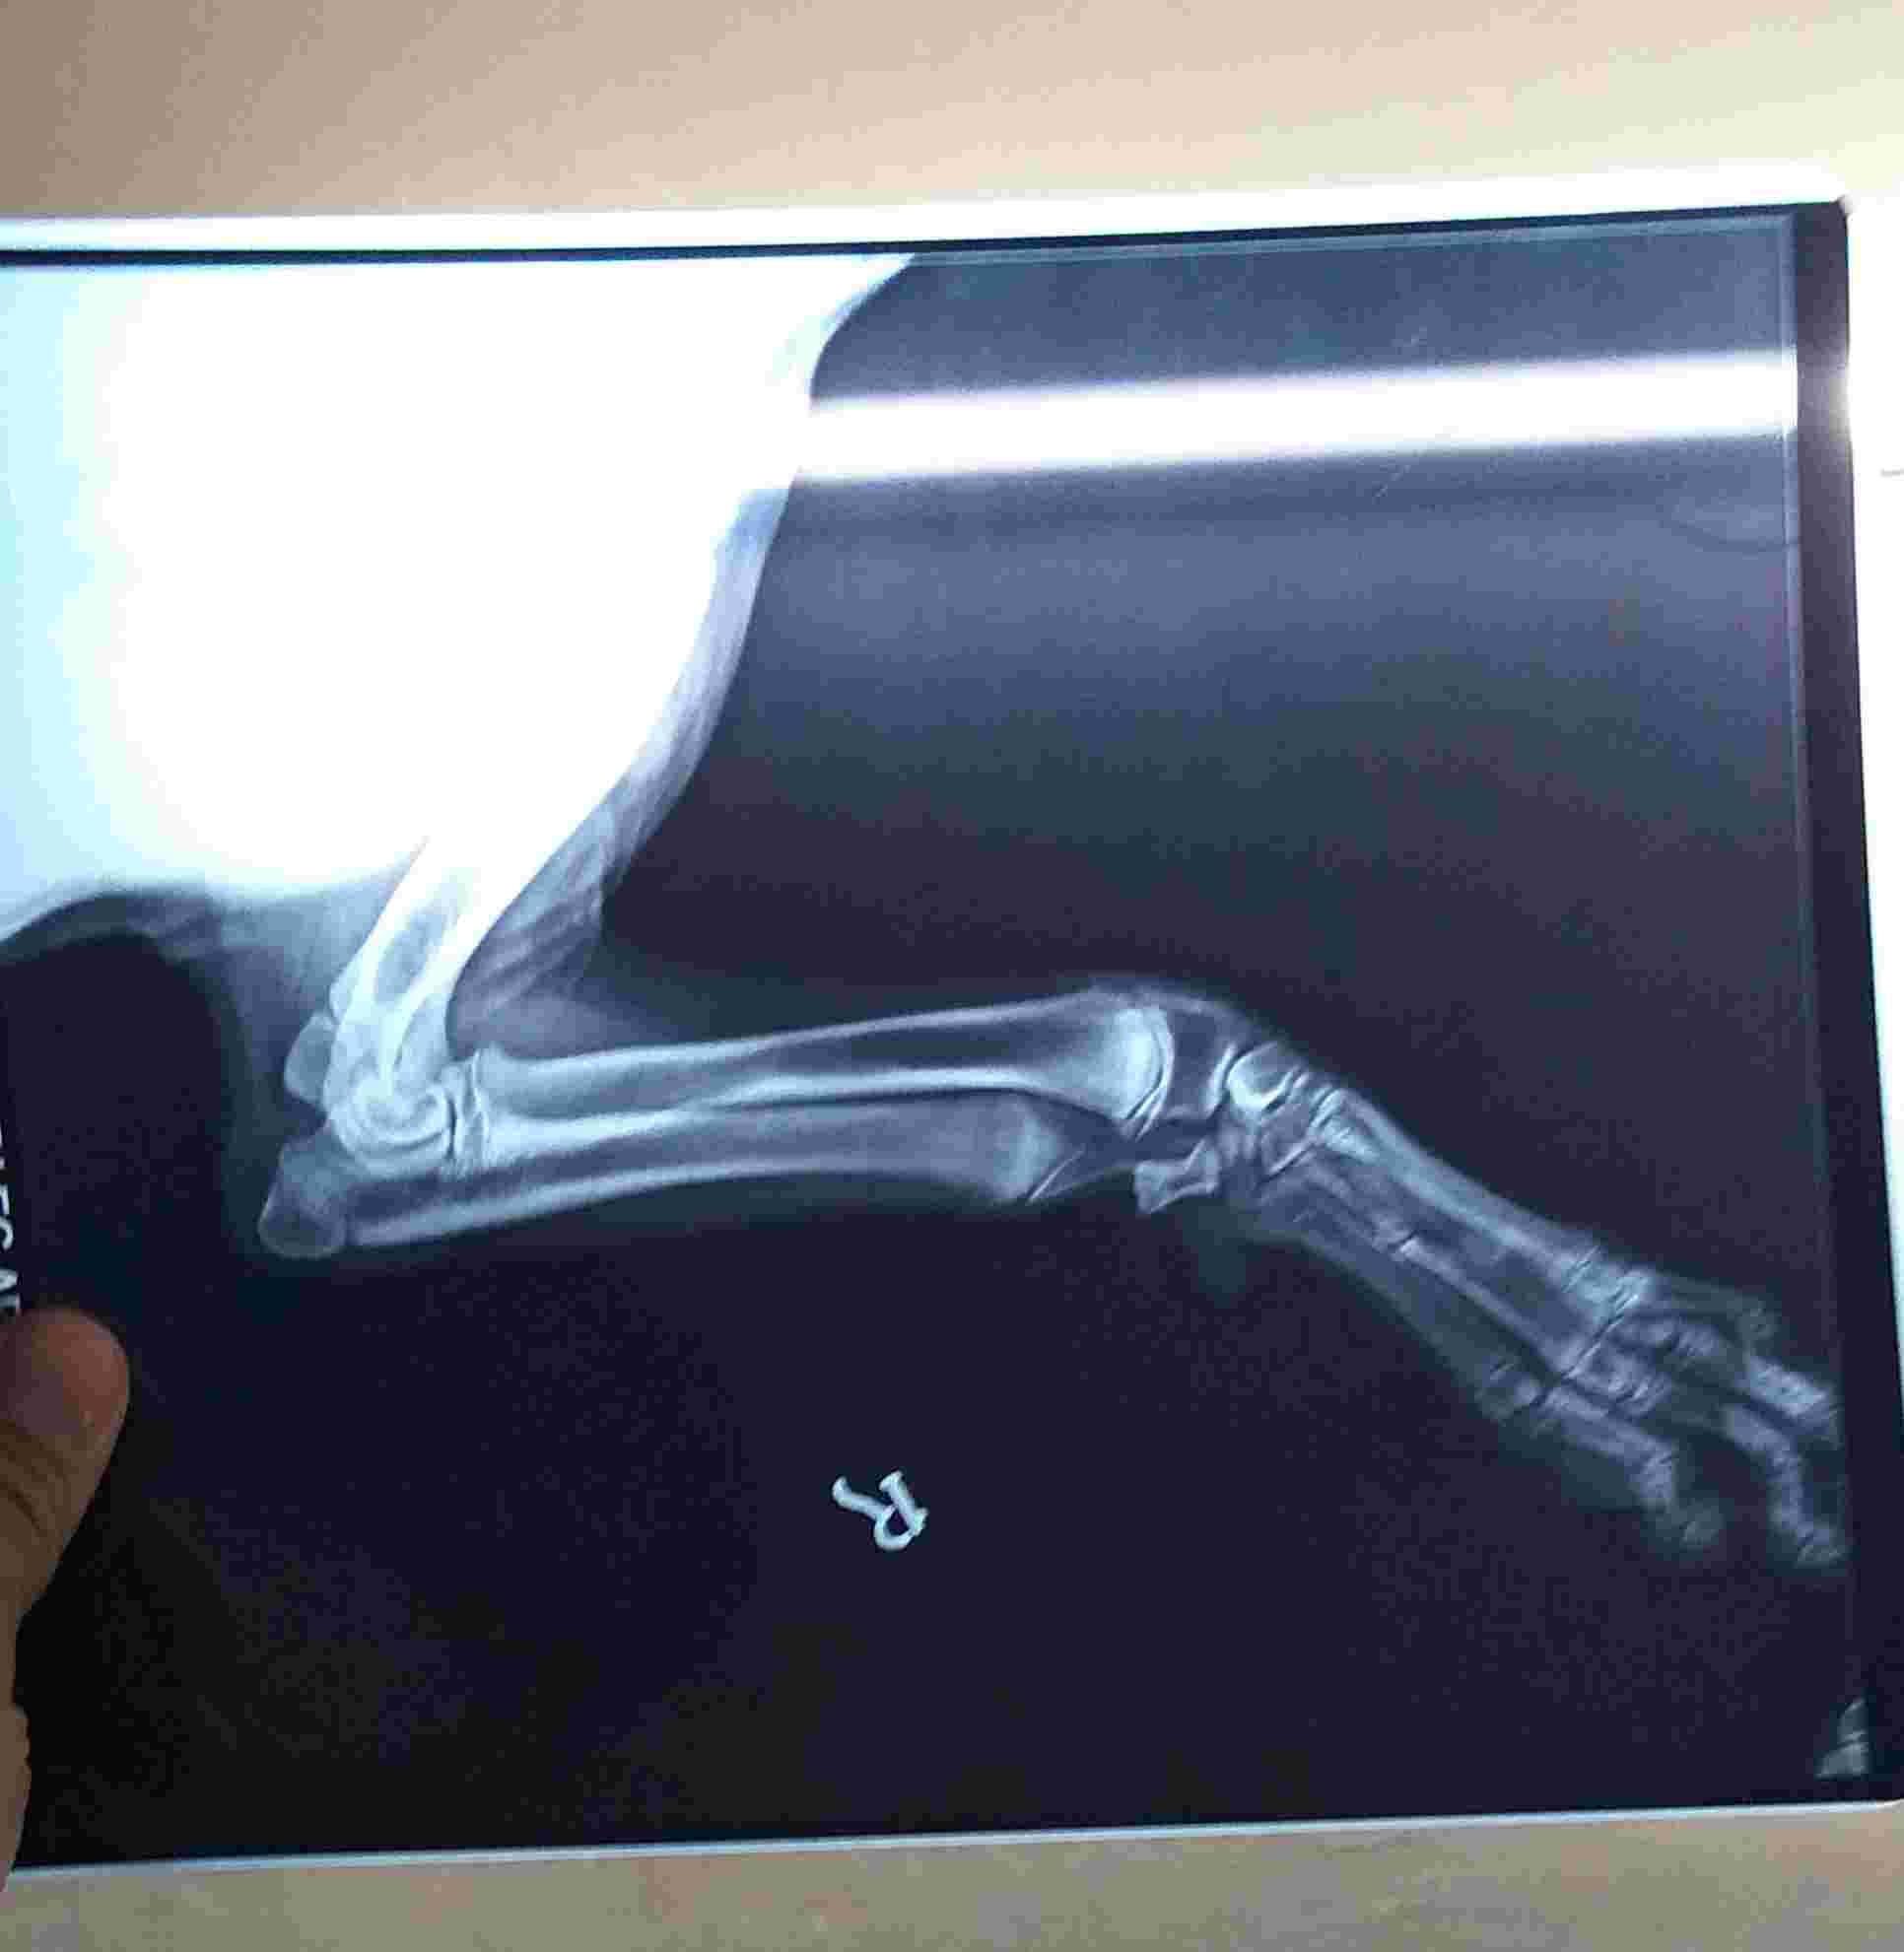

What causes carpal valgas deformity ? Is smooth surface like glossy tiles walking on them or running is the cause of this carpal valgas? If not mention the cause also at his this age of almost 3 yrs if I going to wrap splints on his legs then will this valgas will going to correct or it will going to be like this only? Also I am attaching xrays of his bith front legs kindly see the attachment to confirm me whether valgas is showing in the xrays or not

This can be from his genetics or breeding or can develop after an injury. Splinting the carpus will help prevent the condition from worsening when used during exercise but will not correct the problem. Yes the X-rays show a valgus deformity. This is a dog I would not breed since you don’t want to take the chance of this being passed on to the puppies. I recommend a consult with a board certified orthopedic surgeon to see if there is corrective surgery or any rehabilitation treatment they recommend. Thanks for using Petco Pet Education Center, formerly Petcoach to help you care for Danny.